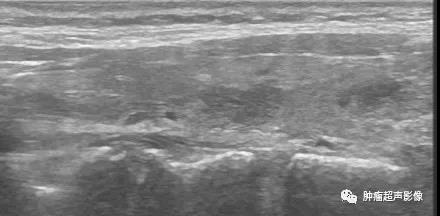

超声表现:急性期超声显示单侧或双侧甲状腺肿大,病灶局限性单发或多发,为形态不规则的低回声,边界模糊不清,回声不均匀,病灶回声从外向内逐渐降低,病灶处甲状腺包膜模糊不清,与颈前肌间的间隙消失,CDFI周边血流多,内部血流少,原有甲状腺血管可穿过病灶(“血管漂浮”),周边无明显环绕血管;颈部淋巴结可见反应性肿大;

超声探头加压低回声区一般压痛明显;

颈部疼痛,双侧甲状腺肿大,形态不规则的低回声,边界模糊不清,回声不均匀,病灶回声从外向内降低,甲状腺前方包膜模糊不清,与颈前肌间的间隙消失,CDFI血流稀少。